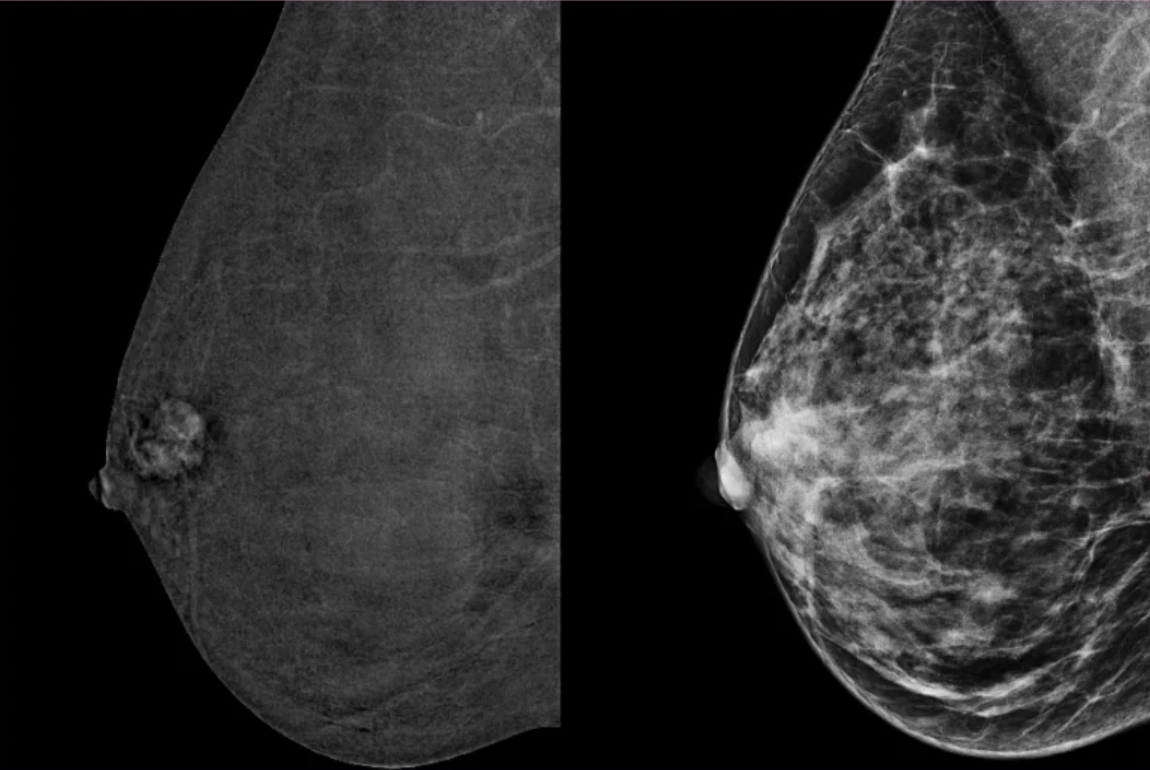

2025 Winter Webinar – Breast Density & Implants